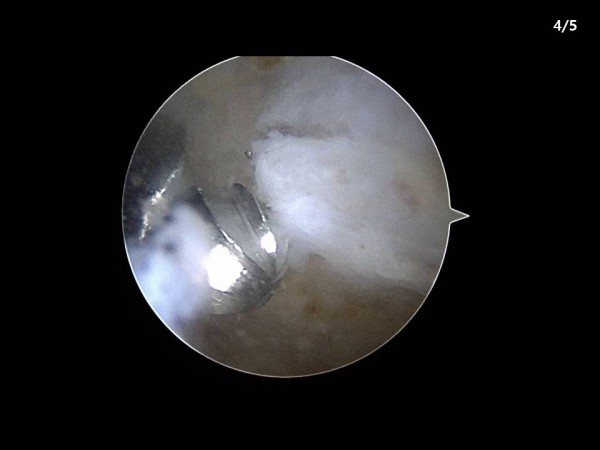

논문 및 학술활동 족부 서있거나 걸을때 악화되는 우측 발뒤꿈치 통증을 주소로 내원한 53세 남자 환자 case report 20.08.24 15:42 1,768 서있거나 걸을때 악화되는 우측 발뒤꿈치 통증을 주소로 내원한 53세 남자 환자 case report : 2019년 대한족부족관절학회 춘계학술대회 / 족저근막염 내시경술을 이용한 치료법 발표 이전글 양측 발에 발생한 중등도 이상의 무지외반증 수술적 교정에 있어 편측 교정과 양측 동시 교정의 임상적 방사선학적 결과 20.08.24 다음글 무지외반증 수술 후 발생한 의인성 무지내반증 치료 결과 20.08.24 목록